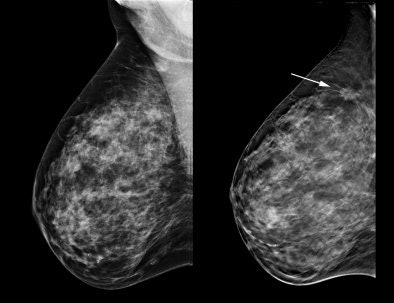

| Tomosynthesis advocates believe the technology can help visualize structures that might be obscured by overlapping tissue on 2D mammography studies. |